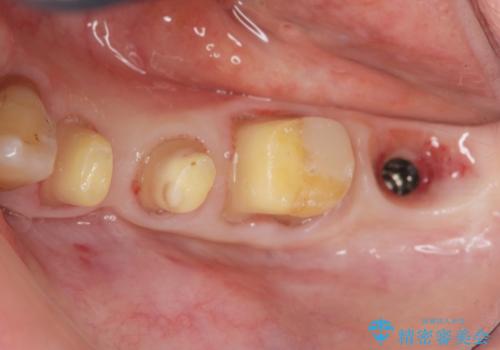

重度の歯周病で再生療法の適応ではない最後方臼歯は抜去行い、インプラント治療、

がたつきの強い天然歯を矯正治療で整えたのち、再生治療、歯周ポケットを除去する歯周外科手術を行いました。

再生療法を行ったことで、抜歯をされてもおかしくなかった歯を、残すことができました。